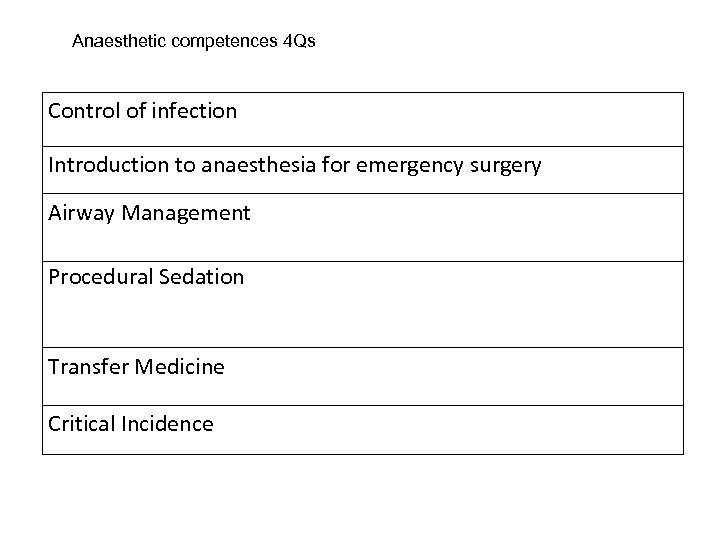

Anaesthetic competences 4 Qs Control of infection Introduction to anaesthesia for emergency surgery Airway Management Procedural Sedation Transfer Medicine Critical Incidence